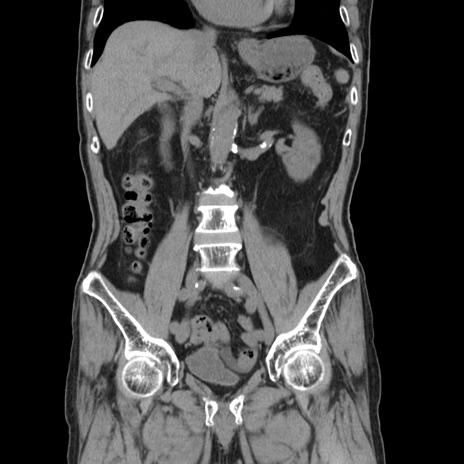

症例24(冠状断像)

【症例】80歳代男性

【主訴】左側腹部痛、嘔吐

【現病歴】本日早朝より左腹部に痛みあり。昼頃嘔吐認めたため、救急要請。

【既往歴】直腸癌(Mile手術)、胆摘

【身体所見】意識清明、BT 35.9℃、BP 221/93mmHg、SpO2 97%(RA) 、腹部:左ストーマ周囲に限局性の腹部膨隆あり。 膨隆部自発痛・圧痛あり・軟。

【データ】WBC 7700、CRP 0.09